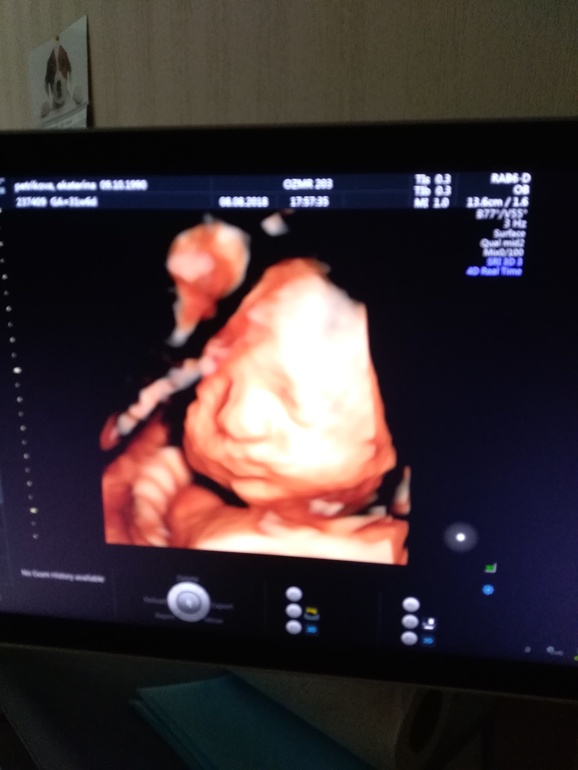

Вчера был последний скрининг. 2 кг, двойное обвитие сохраняется. Щёки у нас знатные. Ротик мой, а нос по моему свекрови.